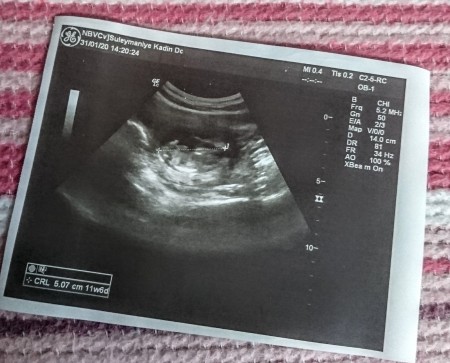

İkili test için gittim dolu oldugu icin yapmadılar normal kontrol oldum bebek iyi dediler baya haraketliydi elleri parmakları ve kocaman göbüşü var dedi doktorumuz hepsini de gösterdi çok şükür :) ikili test işimiz de özel hastaneye kaldı artık

Gebelik haftası 12+0